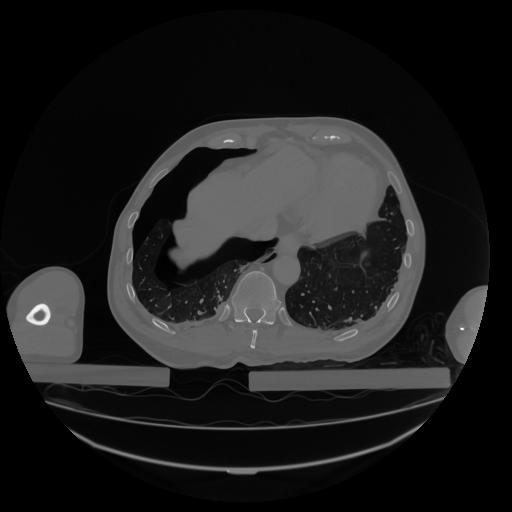

34 CUERPO,CE,Vol,1.0,CUERPO,,